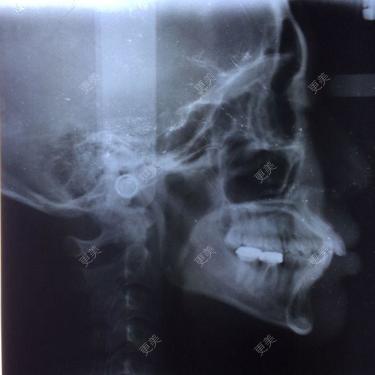

请问我我是骨性龅牙吗?需要通过正颌手术才能改善吗?还是通过矫正牙齿就可以达到一定的效果虽然前牙有深覆盖,安氏二类错颌,但是从软组织影像来看,畸形不是很严重。可以通过正畸来部分改善。

• 虽然前牙有深覆盖,安氏二类错颌,但是从软组织影像来看,畸形不是很严重。可以通过正畸来部分改善。